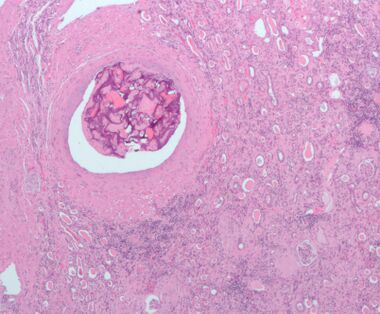

![]() Micrograph of embolic material in the artery of a kidney. The kidney was surgically removed because of cancer. H&E stain. | |

إحداث الانسداد يشير إلى تمرير وإيداع سدادة في تيار الدم. قد تكون مرضية (وفي هذه الحالة تسمى انسداد وعائي)، مثل الانصمام الرئوي، أو علاجية، كإرقاء لعلاج النزيف أو لعلاج بعض أنواع السرطان عن طريق غلق الأوعية الدموية عمدًا لتجويع خلايا الورم.